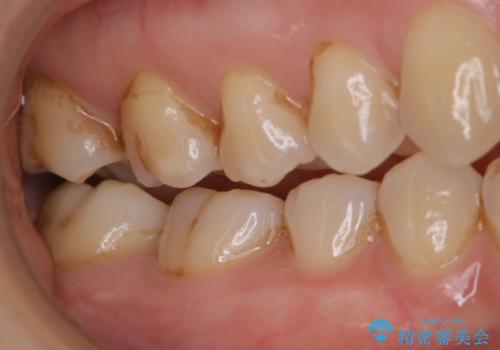

歯磨きをしても奥歯のザラつきが取れない

- 毎日歯磨きをしているのに、奥歯のザラつきが気になるとのことでした。プラーク・歯石・ステインが付着していたためPMTC60分コースを行いました。